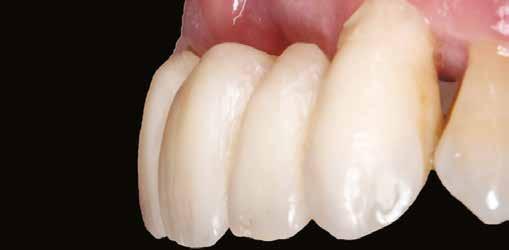

A végleges protetikai ellátást három hónappal az implantációt követően kezdtük meg. Az implantátumok gyógyulása panasz- és tünetmentes volt. Hagyományos, zárt kanalas A-szilikon lenyomatot vettünk (8. a–c ábrák). Egy esetben a gingivális emergenciát sikerült nagy pontossággal lemintázni fényre kötő folyékony kompozit segítségével (Master Flow, Biodinamica; 9. a–c ábrák). Három lítium-diszilikát és egy monolitikus cirkonkorona készült (10. a–b. ábrák), amelyek cementtel rögzültek a végleges protetikai fejeken (Dual RelyX™ U200, 3M; 11. a–b ábrák).

10. a ábra: Végleges lítium-diszilikát koronák. – 10. b ábra: Végleges monolitikus cirkónium-dioxid korona. – 11. a–b ábrák: Klinikai megjelenés tizenkét hónap elteltével. 12. a–b ábrák: Tizenkét hónapos kontrollröntgen-felvételek.